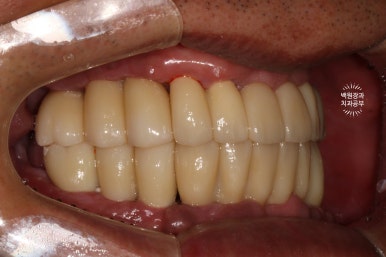

이렇게 보면 측면 모습도 상당히 괜찮고....

잘 보시면 치아와 치아 사이에 틈이 있는 것을 보실 수 있으실텐데요, 이 경계는 앞니 보철물/어금니 보철물의 경계로 추후에 보철물의 수리가 용이하기 하기 위함입니다. 더불어 치실을 쓸 수 있게 하는 공간으로 반드시 필요한 포인트!

이젠 치아가 생겨서, 식사를 하실 수 있게 되었습니다.

잘 제작된 보철물은 앞니로 면도 끊어먹을 수 있어서 환자분들께 크나큰 만족감을 줍니다.